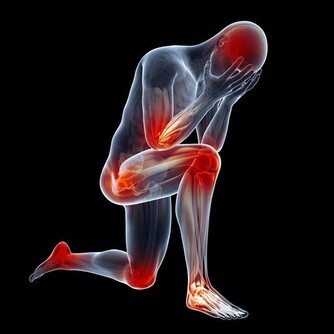

脈搏整齊有規律

脈搏的每一次跳動,都是由一次心臟跳動轉化的,通常每分鐘脈搏的跳動次數就是每分鐘心臟跳動的次數。摸脈主要是摸頻率(快慢)和節律(整齊與否)。正常人平靜時脈搏的頻率在每分鐘50-90次之間,如休息時低於或超過太多都應引起警惕。而節律是指脈搏跳動得是否整齊,正常的心臟節律就像鐘錶的秒針一樣,一下一下非常整齊。